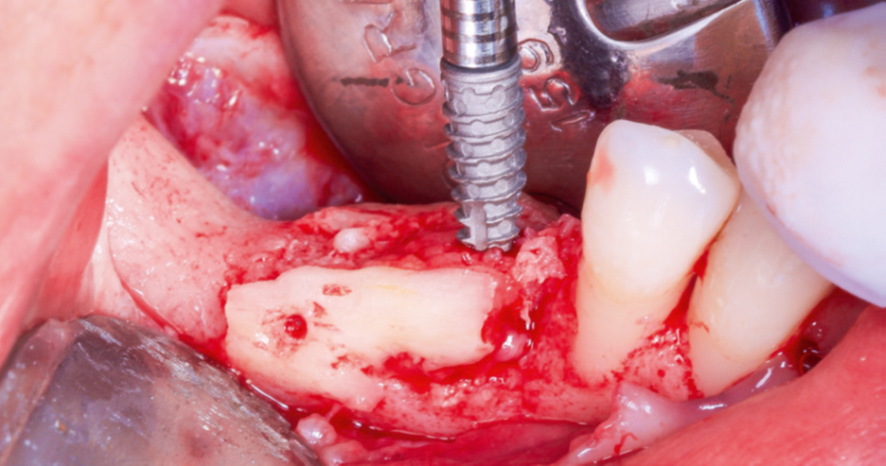

Após a maturação do tecido gengival, procedeu-se ao preparodo leito receptor com incisão e descolamento mucoperiosteal,liberando-se o tecido lingual por meio do alívio da tensão musculardo milo-hióideo (Figura 3) com o descolador de Molt (Supremo Instrumentais). Em seguida, prosseguiu-se com a coleta de osso autógeno do ramo mandibular (área próxima ao leito receptor, do mesmo lado, conforme Figura 4). As lâminas ósseas foram adaptadas e fixadas nas corticais vestibular e lingual com parafusos de titânio (Orth – Implacil Osstem / Figura 5), criando um compartimento do tipo caixa, preenchendo-se o seu interior com osso particulado autógeno (Figura 6). A sutura foi realizada com pontos em colchoeiro horizontal seguidos de pontos simples interrompidos (Figura 7). A cicatrização foi considerada satisfatória.

Após três meses, constatou-se a neoformação óssea adequada.Assim, foram instalados três implantes cone-morse Maestro (Implacil Osstem) com estabilidade primária satisfatória e aproximadamente 20 Ncm de torque de inserção (Figura 8). Após a instalação dos implantes, para ganho de volume tecidual e diminuição da remodelação do tecido ósseo, foi realizada a colocação de enxerto ósseo xenógeno com colágeno (Extra Graft, Implacil Osstem / Figura 9). Três meses após a osseointegração, os implantes foram reabertos para instalação dos pilares protéticos (Ideale, Implacil Osstem) e confecção das coroas provisórias, seguidas da finalização com as cerâmicas definitivas unitárias em zircônia monolítica após mais três meses de terapia (Figuras 9 e 10).